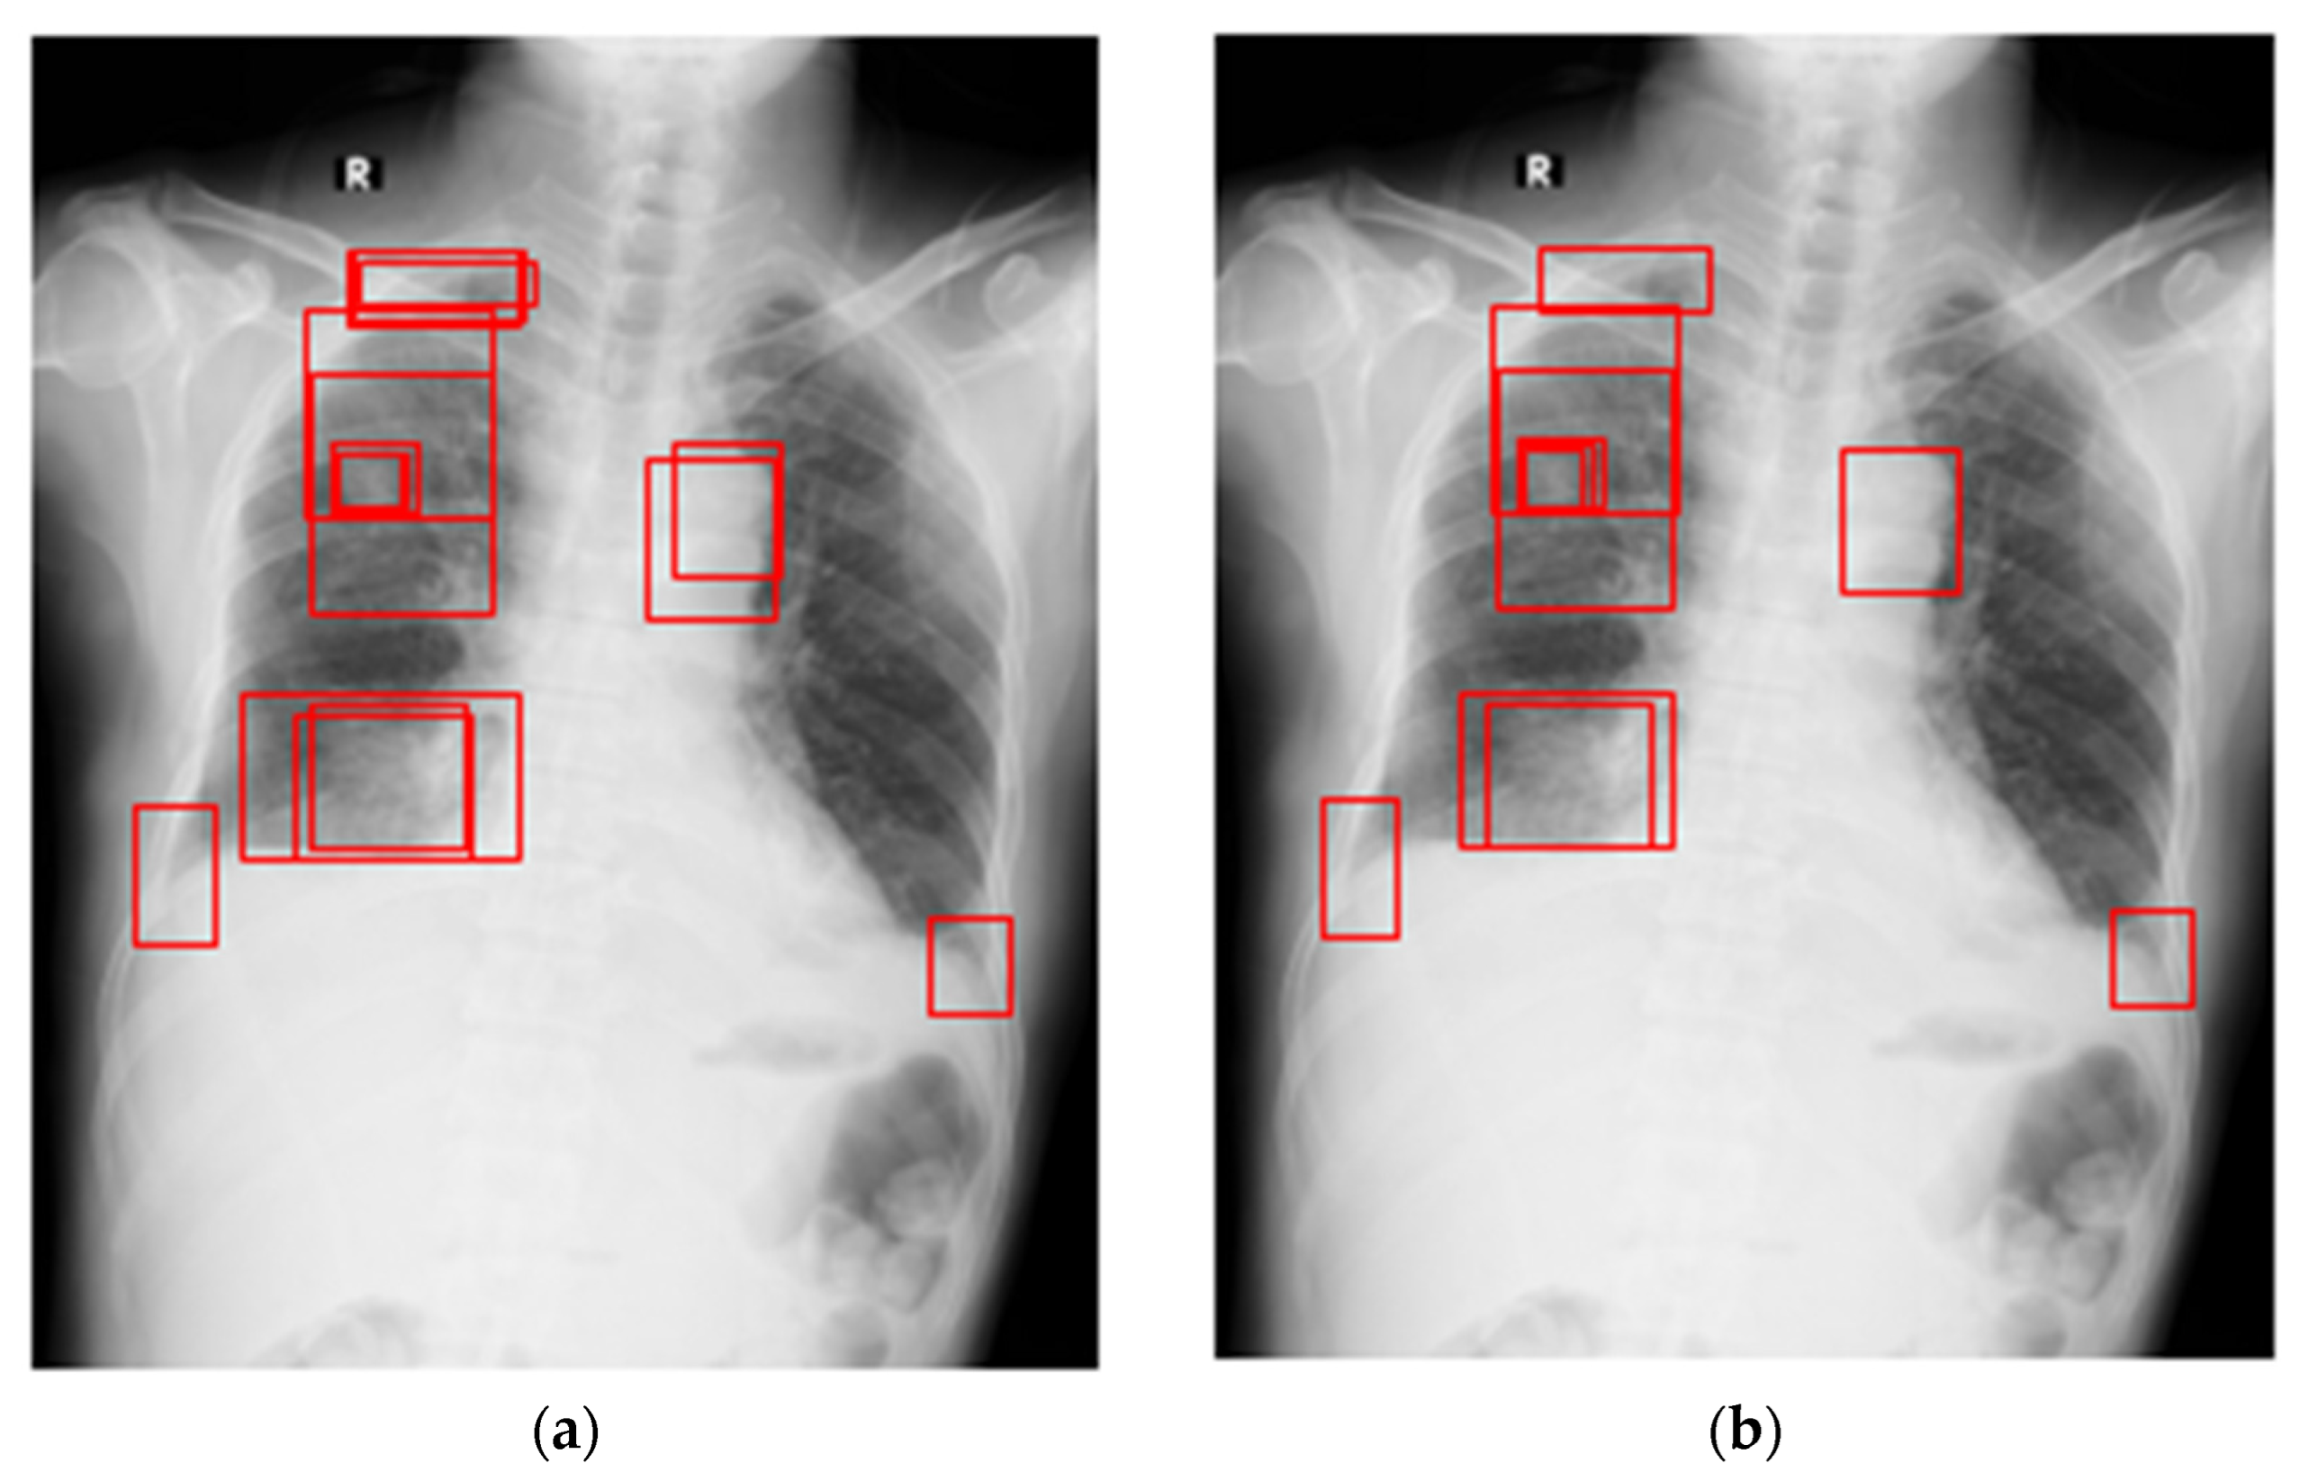

Because the chest X-ray abnormalities were independently labeled by three professional radiologists, many overlaps in annotation boxes were found in the VinDr-CXR dataset. Therefore, the weighted box fusion (WBF) technology [42] was used to reduce the overlap and redundancy of the annotation boxes. In Figure 5, the left image shows the original label and the right image shows the result obtained using WBF. It can be observed that the annotation box was significantly smaller and more concise after pre-processing. In addition, the original chest X-rays had a low contrast and brightness, which may have influenced the learning effect. For this reason, we performed image pre-processing for each sample through histogram equalization, and the results are shown in Figure 6.

Figure 5.

The pre-processing for label box: (a) original label in the VinDr-CXR dataset; (b) optimized annotation result obtained using WBF. The red box indicates the location of the chest abnormality.